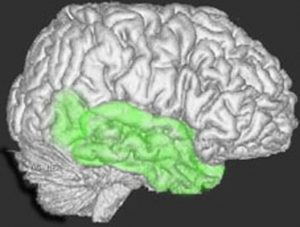

側頭葉の解剖図

側頭葉の解剖図です

側頭葉の解剖図です。表面からは見えませんが,深部の海馬というところには記憶の中枢があります。左側頭葉には言語の中枢もあります。聴覚や味覚,情動などの中枢も側頭葉にあります。

脳の右と左側面から